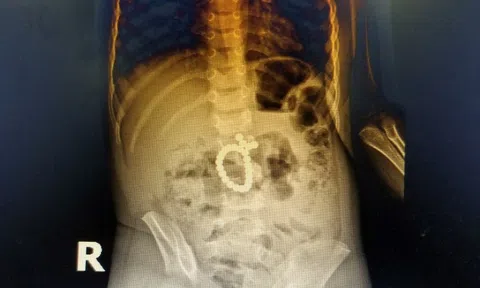

Bác sỹ giật mình trước cảnh tượng hàng chục viên bi nam châm trong bụng bé 3 tuổi

Bé trai 3 tuổi được gia đình đưa đi khám trong tình trạng đau bụng, khi bác sỹ khám thì phát hiện trong ruột bị thủng nhiều vị trí vì chuỗi 25 hạt nam châm.